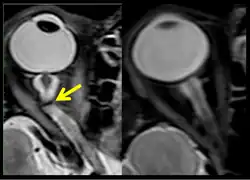

The sixth case of visual changes of an ISS astronaut was reported after return to Earth from a 6-month mission. When he noticed that his far vision was clearer through his reading glasses. A fundus examination performed 3 weeks postflight documented a grade 1 nasal optic-disc edema in the right eye only. There was no evidence of disc edema in the left eye or choroidal folds in either eye (Figure 13). MRI of the brain and eyes days postflight revealed bilateral flattening of the posterior globe, right greater than left, and a mildly distended right optic nerve sheath. There was also evidence of optic-disc edema in the right eye. A fundus examination postflight revealed a "new onset" cotton-wool spot in the left eye. This was not observed in the fundus photographs taken 3 weeks postflight.[5]